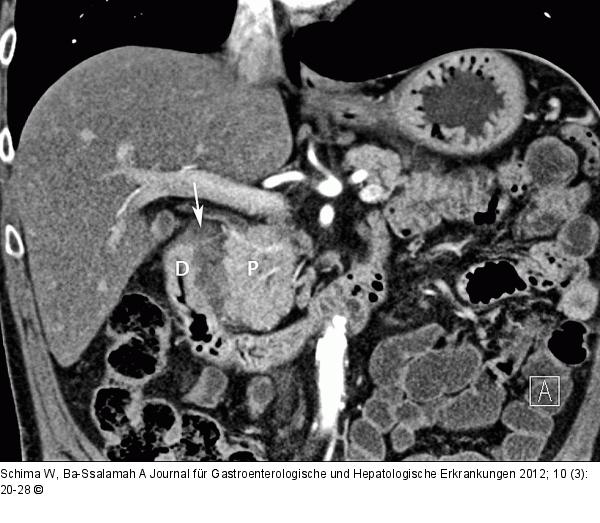

Abbildung 8: Groove-Pankreatitis Groove-Pankreatitis. Die kontrastmittelverstärkte MDCT zeigt typisch den Entzündungsprozess zwischen Pankreaskopf (P) und Duodenum (D) lokalisiert. |

Groove-Pankreatitis. Die kontrastmittelverstärkte MDCT zeigt typisch den Entzündungsprozess zwischen Pankreaskopf (P) und Duodenum (D) lokalisiert. |